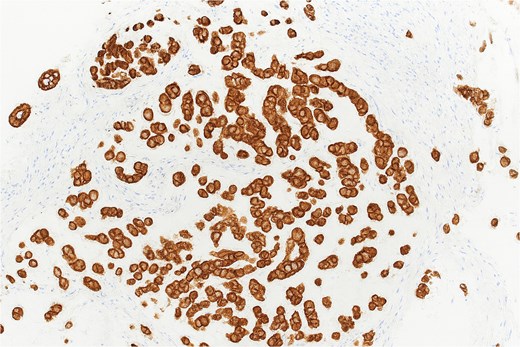

Histopathological analysis revealed chondroid matrix with nests of atypical epithelioid cells infiltrating the colonic mucosa. Immunohistochemistry showed strong nuclear positivity for brachyury and diffuse pancytokeratin staining, consistent with metastatic chordoma (Figs 1– 3).

Immunohistochemistry showing strong nuclear positivity for brachyury, confirming the diagnosis of metastatic chordoma (×10).

Pancytokeratin immunohistochemistry demonstrating diffuse membranous and cytoplasmic positivity in tumor cells (×40).